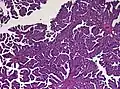

The tumor is neuroectodermal in origin and similar in structure to a normal choroid plexus. They may be created by epithelial cells of the choroid plexus. Papillary fronds lined by bland columnar epithelium are visible under the microscope. Normal absences include mitotic activity, nuclear pleomorphism, and necrosis.[10] Tumors have positive immunohistochemistry for cytokeratin, vimentin, podoplanin, and S-100.[11] Up to 20% of choroid plexus papilloma patients may test positive for glial fibrillary acidic protein (GFAP).[12] Studies have found that fourth ventricle cancers express more S100 than lateral ventricle tumors, and older patients (over 20 years) express more GFAP and transthyretin than younger patients.[13] Some individuals with choroid plexus papilloma have germline TP53 gene mutations, according to genetic analyses.[14] These cancers rarely exhibit nuclear p53 protein positivity. Aicardi syndrome, hypomelanosis of Ito, and 9p duplication are syndromic correlations of choroid plexus papilloma.

Plexuspapillom Overview

Plexuspapillom Overview